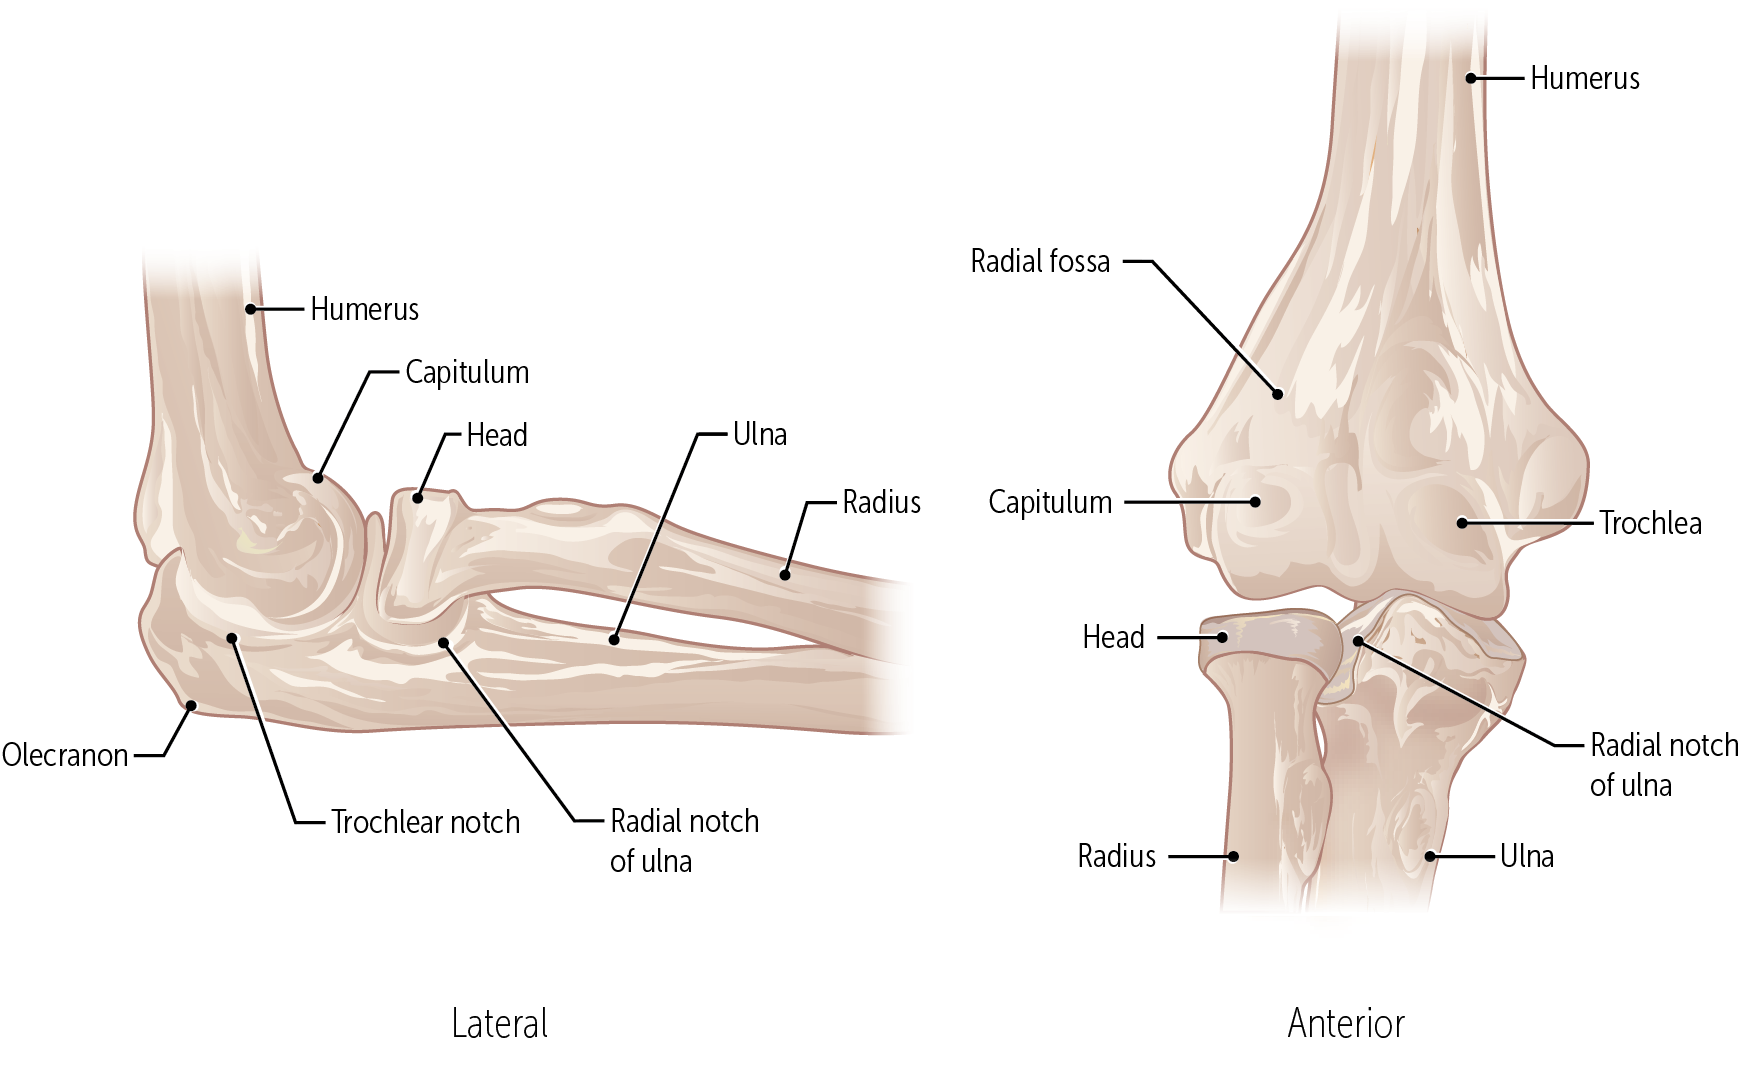

The trochlea and the capitulum (the condyles) are the most distal surfaces of the humerus, where it articulates with the forearm bones at the elbow joint

What bones connect to the humerus at the elbow?

The radius and ulna

What are the three articulations in the elbow joint?

The humerus-ulna articulation

The humerus-radius articulation

The proximal radius-ulnar articulation

The __________ forms a hinge joint, used to flex and extend the forearm

humerus-ulna articulation

The __________ allows the radius to rotate because the concave head of the radius fits onto a round humoral capitulum.

humerus-radius articulation

The __________ is a articulations in the elbow joint that does not directly contribute to motion at the elbow.

proximal radius-ulnar articulation

The rounded __________ of the humerus allows the head of the radius to rotate within the radial notch of the ulna

capitulum